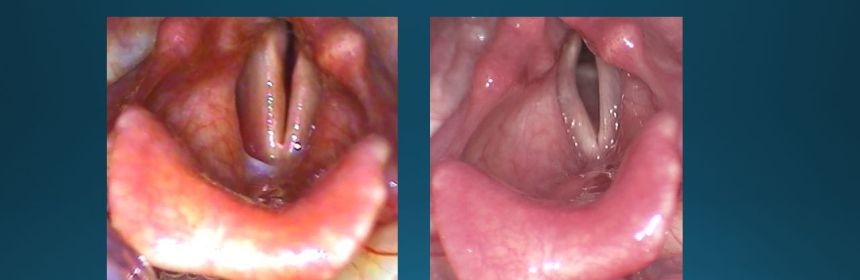

Ekteki fotoğrafta çift taraflı ses teli felci olan bir hastamızın tedavi öncesi (sol) ve sonrası (sağ) ses tellerini görebilirsiniz.

İki taraflı ses teli felci – Ameliyat öncesi ve sonrası görüntüleri – Prof.Dr. Haldun Oğuz